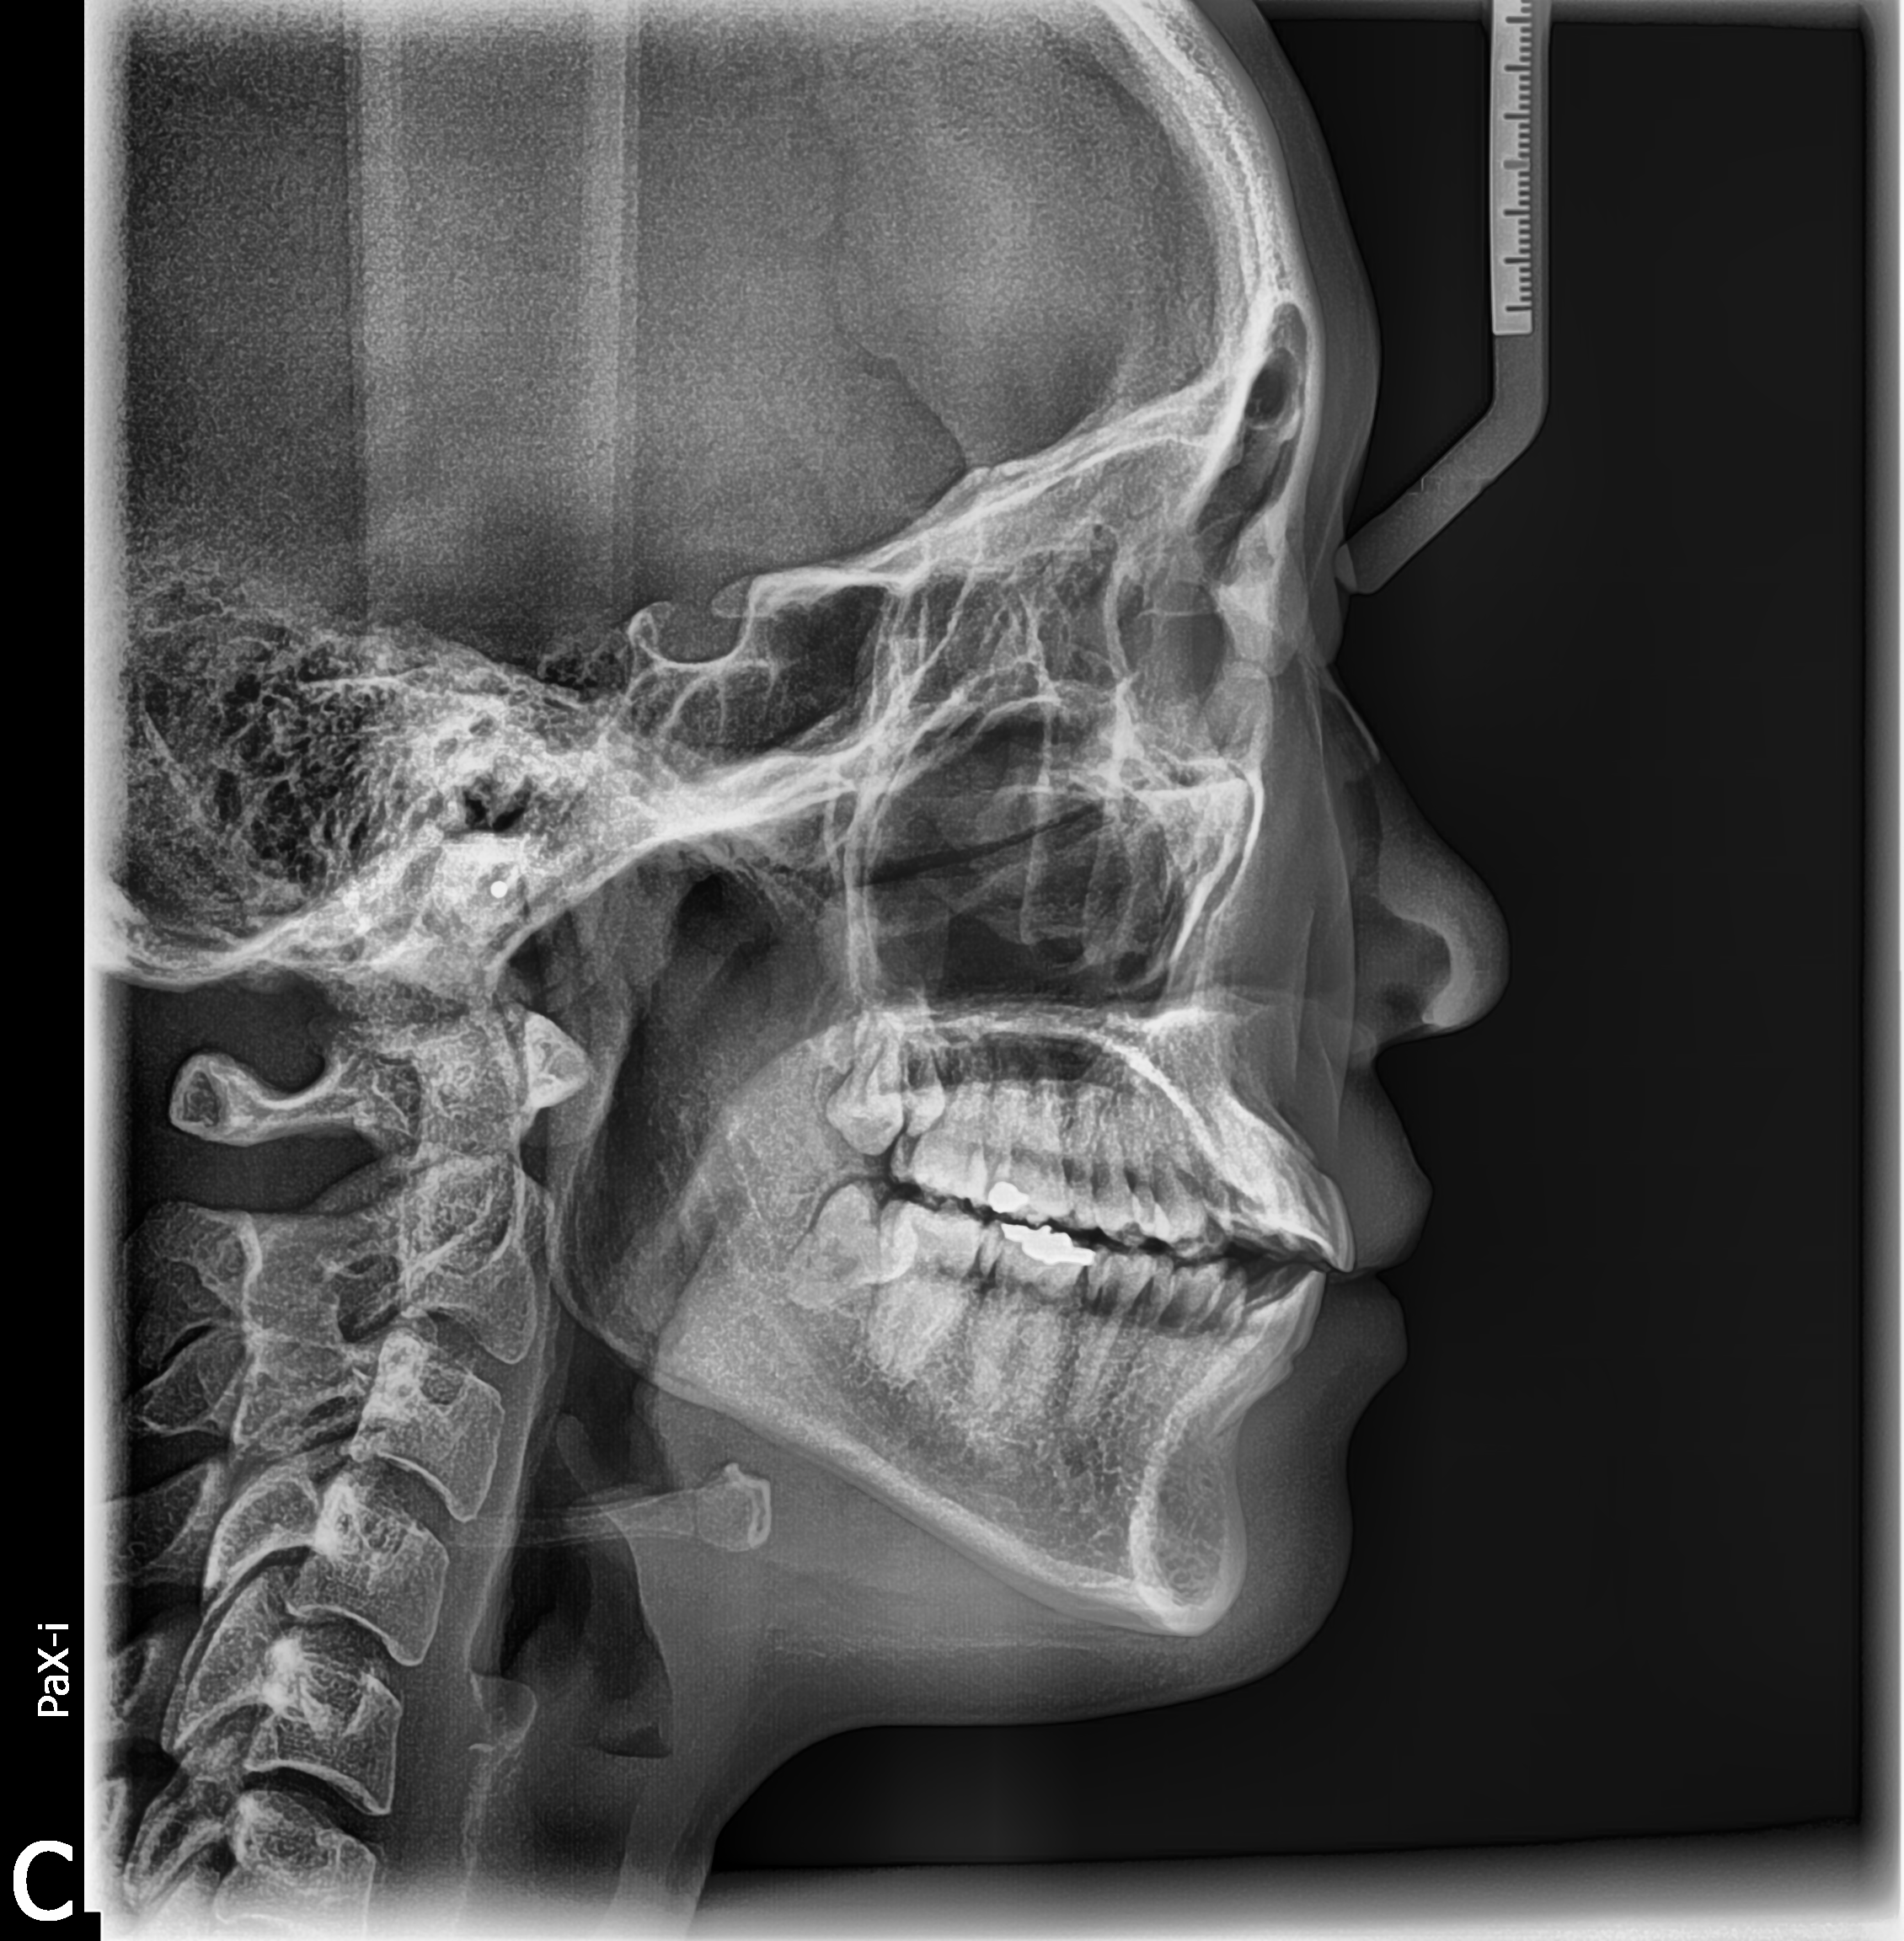

Technique de balayage du scanner

Taille d’image (21 x 23 cm) pour un diagnostic essentiel

Temps d’acquisition : 12.9 secondes

Qualité d’image en Haute Définition

Le Scan Ceph est un appareil de radiographie dentaire avancé, conçu pour fournir des images d'une précision exceptionnelle. Ce modèle propose des vues panoramiques, céphalométriques, et 3D, s'adaptant ainsi aux besoins variés de la pratique dentaire.

Grâce à la technologie de pointe CBCT, il minimise l'exposition du patient offrant une sécurité accrue.

Spécialement développé pour les cliniques dentaires et les cabinets maxillo-faciaux, le Scan Ceph assure des diagnostics précis, une planification optimale des implants, et une évaluation détaillée des structures osseuses et dentaires.